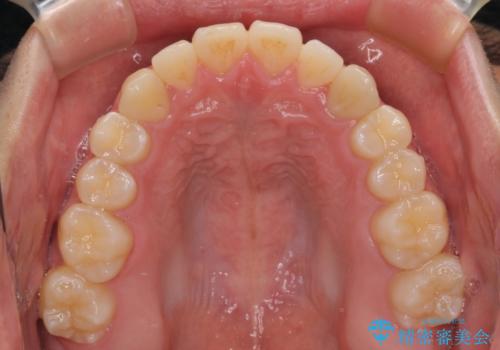

受け口傾向の骨格であり、前歯はクロスバイトまたは切端咬合となっており、叢生は警備であったため、下顎を中心に歯列全体の後方移動を行い、IPR(歯と歯の間を削る)によってデコボコが解消するように設計し、インビザラインにより治療を行うこととしました。

受け口傾向のインビザライン矯正は比較的治療を行いやすいため、きれいに仕上げることができました。舌の突出癖が顕著であったため、改善のためのトレーニングをしっかりと行っていただきました。